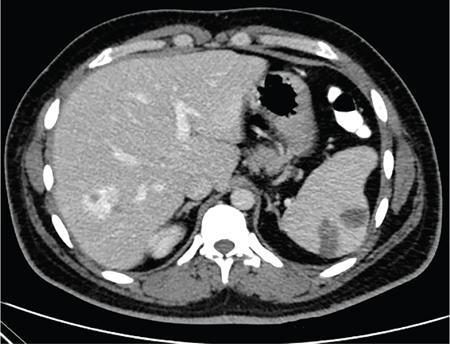

Vijay Kumar K.R. CONGENITAL SPLENIC ABNORMALITIES A multitude of variants and pathologies affect the spleen and it is pertinent for a radiologist to be aware of the common imaging appearances of the same. The spleen begins to develop in the fifth week of gestation from a mass of mesenchymal cells that condense between the two leaves of the dorsal mesogastrium. Several such aggregates fuse to form the lobulated embryonic spleen. The spleen is translocated to the upper left side of the abdominal cavity due to rotation of the stomach and differential growth of the dorsal mesogastrium. The mesogastrium fuses with the peritoneum over the left kidney and forms the splenorenal ligament. The lienorenal ligament fuses dorsally and the splenic artery courses behind the peritoneum as it enters the splenorenal ligament. The portion of dorsal mesentery between the stomach and spleen forms gastrosplenic ligament. Differentiated mesenchymal cells form the parenchyma, connective tissue and capsule of the spleen. The foetal spleen shows lobulations, which normally disappear before birth. However, they may persist along the medial part of the spleen. Sometimes a persisting portion of the spleen may extend medially and anteriorly over the upper pole of the left kidney. It may be mistaken for a space-occupying lesion arising from the kidney. Rarely it may extend posterior to the upper pole of the left kidney, displacing it anteriorly (Fig. 9.22.1.1). The notches and clefts along the superior borders are vestiges of the grooves that initially separated the foetal lobules. They may be 2–3 cm deep. They may mimic a splenic laceration in a patient with abdominal trauma, and the embedded peritoneum at the waist may simulate splenic infarction or haematoma. Hence caution should be exercised. A normal spleen which does not have a fixed ligamentous attachment can change position within the abdomen and is hence known as a wandering spleen. The spleen is normally anchored by the gastrosplenic and lienorenal ligament. Absence or weakness of one or more ligaments that affix the spleen. The spleen with its vascular pedicle as the sole attachment can become a hypermobile intraperitoneal organ. Rarely, the spleen may be normal in position with a wandering accessory spleen. Pregnancy (due to hormonal effects), prune belly syndrome, splenic cysts, malaria, Hodgkin’s disease and lymphangioma. Some of the affected patients may be asymptomatic and diagnosis may be incidental. Clinically it presents as a mobile, palpable, notched mass. Pressure on the vascular pedicle or torsion causes symptoms such as acute abdominal pain, nausea and vomiting. Torsion involving the tail of the pancreas may present as pancreatitis. Confirms the absence of spleen in the left upper quadrant of abdomen with identification of splenic tissue at an ectopic site. Power Doppler, colour Doppler and duplex sonography allow for the identification of blood flow in the splenic vessels and parenchyma. Intermittent torsion may be responsible for an enlarged spleen. Pathognomonic feature of wandering spleen is absence of the spleen in the upper abdominal cavity and presence of a well-demarcated, homogeneously enhancing mass of soft tissue in the pelvis or abdomen. Sometimes a wandering accessory spleen can be visualized as a long vascular pedicle connecting a small mass to the splenic vessels (‘jokari sign’). It can locate ectopic splenic tissue and can also indicate the viability of the tissue. Splenic vessel anatomy can be well demonstrated. 99mTc-sulphur colloid scintigraphy and heat denatured 99mTc-labelled red blood cell imaging provide useful information regarding size and location of splenic tissue. Torsion is indicated by lack of tracer activity in a previously demonstrated wandering spleen. Twisting and torsion of splenic artery can be demonstrated by celiac arteriography. The venous phase may demonstrate splenic vein obstruction with collateral circulation and varices. A congenital focus of normal splenic tissue that is separate from the main body of the spleen is known as an accessory spleen. It results from the failure of fusion of some embryonic splenic buds within the dorsal mesogastrium. Its incidence varies from 10% to 30% on autopsy examinations. They vary from a few millimetres to several centimetres in diameter. They most commonly are found around the splenic hilum. The second most common location is the pancreatic tail. They can also be found in the stomach wall, omentum, mesentery, large bowel and scrotum. Reveals a round or oval mass of tissue around the splenic hilum that is isoechoic with the main spleen. On noncontrast images they are isodense to the main spleen. CECT reveals serpiginous enhancement on arterial phase followed by homogeneous enhancement on venous phase-like spleen (Fig. 9.22.1.2). Accessory spleen is mildly hypointense to the spleen on T1 images and isointense on T2 images. Contrast administration reveals enhancement similar to that of spleen on the arterial, portal and late phases. It is isointense to spleen on DWI images with similar ADC values. 99mTc-sulphur colloid scintigraphy and heat denatured 99mTc-labelled red blood cell imaging show functional uptake in splenic tissue and differentiate splenule from other masses. PET CT-FDG avid mass can mimic tumour. Surgical resection is the preferred mode of treatment in the background of hypersplenism or lymphoma. It is characterized by an ectopic splenic tissue or an abnormal connection between the gonad and the spleen. The left side is more commonly involved than the right side. The accepted theory is that splenic gonadal fusion occurs due to abnormal attachment of the splenic anlage in the left dorsal mesogastrium with the left urogenital fold, during the fifth to eighth weeks of gestation. It has a higher male preponderance and can interfere with left testicular descent and closure of processus vaginalis. It commonly presents as inguinal hernia and cryptorchidism. The spleen and gonad are attached by a fibrous or splenic cord across the peritoneal cavity. It is associated with limb defect syndrome, cleft palate, micrognathia, anal anomalies, craniosynostosis, spina bifida, cardiac malformations, thoracic malformations and diaphragmatic hernias. This is not associated with congenital anomalies. Shows a well-defined scrotal mass with echotexture similar to that of spleen. Confirms splenic tissue in inguinal or scrotal area. It is characterized by the absence of spleen with duplication of right-sided structures. (Right isomerism). It has a slight male preponderance with an incidence of 1 in 40,000 live births. It has a poor prognosis due to its high association with congenital cardiac abnormalities (Fig. 9.22.1.3). It is of uncertain aetiology, and maybe associated with the mutations of CFC1 gene, SHROOM3 gene etc. Delayed development of embryonic curvature can be another cause. It is also theorized that it can be caused due to vascular compromise by pressure on splenic blood supply from adjacent structures. Splenectomy – Usually has a surgical history and is not accompanied by associated anomalies. It is a heterotaxy syndrome associated with multiple spleens and duplication of left-sided structures. (Left isomerism). It has an equal gender predilection with a slightly higher female preponderance. It has a fairly better prognosis than asplenia and is associated with a lesser incidence of cardiovascular anomalies (Fig. 9.22.1.4). It is of uncertain aetiology, and maybe associated with the mutations of CFC1 gene, SHROOM3 gene etc. Accelerated development of embryonic curvature can be another cause. SPLENIC INFECTION AND ABSCESS The infection of the spleen can show three patterns. Fungal and granulomatous infections usually present with multiple micronodules. A pyogenic abscess usually manifest as a solitary lesion. Imaging of diseases causing splenic nodules is never the sole basis for diagnosis. The clinical presentation and laboratory testing (tumour markers, tuberculosis testing and bone marrow biopsy) help in establishing an accurate diagnosis. The imaging findings are nonspecific and the nodules may vary in size from a few millimetres up to 2 cm in diameter. They maybe hypoechoic on ultrasound and hypoattenuating on CT. They are of low signal intensity on T1-weighted sequences and vary from hypointense to hyperintense on the T2-weighted sequences. The nodules show no enhancement or show ring enhancement after contrast study. Healed granulomas are seen as scattered, discrete, small calcifications in an otherwise normal spleen. With increasing number of immunocompromised patients, such as oncology patients undergoing aggressive chemotherapy, critically ill patients in intensive care units, injection drug abusers, and HIV-infected patients, there is rise in the incidence of splenic abscess. For splenic abscess to develop, it may require the presence of bacteremia (sepsis and septic emboli) and altered splenic architecture, which is caused secondary to a haematoma, infarct, or sickle cell disease. Abscesses can also develop from the extension of infection from adjacent organs, like in cases of infected pancreatitis and perinephric abscess, which are less common. In about 20% of cases, cause or source could not be discovered. Abscesses can be unilocular or multilocular, solitary or multiple, depending on the causative organisms and patient’s immunity. Mortality ranges from 15% in otherwise healthy patients with unilocular splenic abscess to 80% in immunocompromised patients with multiple abscesses. Abscesses which are multilocular, gas-containing or due to gram-negative bacillus show poor prognosis. A pyogenic abscess is usually solitary, unilocular/multilocular, but it can also be multifocal. These are uncommon and are reported in 0.14%–0.70% of large autopsy series. Most common presentation is fever (92%), left upper abdominal pain (77%) and leucocytosis (66%). Other symptoms are left pleural effusion and splenomegaly. It can be solitary or multiple, unilocular or multilocular. The appearance of splenic abscess depends on the stage of development. In the early stages of the disease, an abscess appears as an ill-defined mass later developing into a complex collection with septations, debris and sometimes gas. In later stages, after a capsule is developed, the lesion becomes well defined. Left pleural effusion is seen in around 42% of cases. Left lung base atelectasis in 20% of cases and splenomegaly is seen. Abscess with air can be identified based on the presence of extraluminal gas or air–fluid levels in the left upper quadrant. Ultrasonography has a sensitivity of 75%–98% in detecting splenic abscess. This is a very useful modality in patients who are bedridden, with renal impairment and for assessment of small splenic lesions (Fig. 9.22.2.1). Ill-defined hypoechoic mass mimicking a mass is seen in the early phase of the infection and a complex mass with internal septations, debris, rarely acoustic shadowing caused by gas is seen in later stages. The capsule appears as a thin hyperechoic rim. It is noninvasive, speedy, and a modality with high sensitivity (92%–98%). It helps in differentiating unilocular from multilocular lesions and, gives exact anatomical localization and information about perisplenic area, which later helps in planning-guided management procedures. An abscess is seen as a hypodense collection or complex cystic lesion with enhancing rim on the postcontrast study (Fig. 9.22.2.2). CT may help in identifying concurrent areas of infection and, thus, the source of infection. On CT, an abscess may look similar to an infarct, haematoma, or neoplasm. An infarct lacks mass effect, unlike abscess or tumour (Fig. 9.22.2.3). The presence of gas within the lesion is diagnostic of abscess; however, this finding is rare. Splenic abscesses show low signal on T1-weighted images and high signal on T2-weighted images compared with the normal spleen. Minimal to intense peripheral enhancement is seen after IV administration of gadolinium. But MRI is not routinely done, as many patients are clinically unstable. This plays a limited role in the detection and localization of splenic abscess. A nonspecific filling defect is seen on a 99mTc-sulphur colloid scan within spleen if the size is more than 2 cm in diameter. Normal inherent splenic activity on 67Ga scans and 111In-labelled leukocytes scans obscures any kind of inflammatory focus in the spleen, giving rise to false-negative examination. 67Ga scans are nonspecific as tracer uptake can be seen in neoplastic conditions such as lymphoma. Detection and characterization of the abscess are better done if 99mTc-sulphur colloid scan is done prior to 111In-labelled leukocytes scan. FDG PET/CT can also detect the site of infection but not used in the diagnosis of splenic abscess. Early diagnosis of an abscess is prompted for a better outcome. Based on laboratory findings, appropriate antibiotic therapy initiated. USG or CT-guided percutaneous aspiration is tried if the abscess is less than 5 cm in size, and for larger abscesses, percutaneous drainage procedures are done preserving the spleen. Splenectomy is reserved for complicated infections. Fungal abscesses are usually seen in immunocompromised patients with neutropenia such as patients with acquired immunodeficiency syndrome (AIDS), on chemotherapy and immune suppressive agents, and with lymphoproliferative disorders. With the advent of aggressive chemotherapy, the incidence of splenic fungal infections has increased. Approximately 7% of patients with acute leukaemia have hepatosplenic fungal infections. Multiple microabscesses are common. Hepatosplenic candidiasis lesions are very small, and before the advent of CT and MRI, their detection was too difficult. They measure in the range of 5–10 mm in diameter; however, they may be even miliary (<5 mm). Infections are mostly caused by candida species. Other organisms are aspergillus, Histoplasma and Cryptococcus. Imaging characteristics depend on the stage and severity of neutropenia. In cases of chronic disseminated infections with poor neutrophil counts, sometimes lesions are not visible as the host fails to produce an immune response. Lesions become apparent once neutrophil counts improve. Patients presenting with fever and splenomegaly are not improving on conventional antibiotic therapy, and with associated immunocompromised status, fungal infections are to be considered. No single imaging is specific or sensitive in establishing the diagnosis. Serial imaging is needed to detect hepatosplenic involvement; however, tissue diagnosis is the gold standard. Four different patterns are seen in hepatic candidiasis. Multiple, small, homogeneous hypoechoic nodules are the most common finding. Less commonly wheel-within-a-wheel appearance (i.e. the target sign) is seen in the early stage of infection. The first wheel is the peripheral hypoechoic zone of fibrosis and an echogenic second wheel of inflammatory cells around a central hypoechoic nidus containing necrosis and fungal elements. Later these lesions evolve into Bull’s eye lesion where there is a central echogenic focus surrounded by a hypoechoic halo. Lesions become small and hyperechoic with various degrees of posterior acoustic shadowing, with or without calcification, or they may even disappear later in the course of the infection. Splenic nodules are hypodense lesions measuring in the range of 5–10 mm. Only 30% of cases are detected in noncontrast studies. They often have low attenuation, although there can be a focus of high attenuation or a ‘wheel-within-a-wheel’ pattern. Peripheral ring of enhancement is noted in around 70% of cases in the arterial phase of CT, and it is said to disappear on the portal venous phase. There is no significant difference in the detection of the lesions between arterial and portal venous phases of contrast studies. MRI is said to be the investigation of choice for diagnosis of hepatosplenic candidiasis and is superior to CT and USG, especially when short-time inversion recovery sequence is used. MR imaging is also used to monitor the response to antifungal therapy. Based on MRI findings different phases of hepatosplenic candidiasis are described. Lesions are small, measuring less than 1 cm in diameter. They show mildly hypointense on the T1-weighted images and markedly hyperintense on the T2-weighted images. In 2 weeks to 3 months, acute lesions are transformed into subacute lesions. The lesions reveal mildly increased signal on both T1- and T2-weighted sequences. On all sequences, a peripheral ring of very low signal intensity is seen. Following the gadolinium administration, the central region of the lesions show enhancement; however, the peripheral ring continues to have low signal intensity, making them more obvious. It takes from 3 months to more than 1 year for the healed fungal foci composed of fibrous tissue of differing densities and degrees of vascularization to appear on MRI. The lesions measure 1–3 cm, become irregular, and the central area disappears. Chronic healed fungal abscesses have low signal intensity on T1-weighted images and are isointense to mildly hyperintense on T2-weighted images. No perilesional dark ring is noted. These lesions are moderately hypointense on early postgadolinium images and minimally hypointense on delayed postgadolinium images. Mycobacterial tuberculosis infections are mainly seen in immunocompromised patients. Spleen involvement is seen in disseminated, miliary infection in about 80%–100% of autopsy cases; however, it is documented less on imaging. Splenic tuberculosis is seen in the form of nodules measuring ∼ 0.2 and 1 cm in diameter. The macronodular form is very rare (Fig. 9.22.2.4). Hypoechoic pattern is seen. Hypoattenuating nodules with lymphadenopathy noted. Depending on the different stages of the tubercular process, intensities on T1- and T2-weighted images vary. On contrast-enhanced T1-weighted images, lesions most often show peripheral enhancement less commonly gradual peripheral enhancement with complete filling is noted. It is also called as Mycobacterium intracellulare infections. These are also typically seen in immunocompromised patients. Splenomegaly with multiple, low attenuation nodules is seen. Associated findings such as hepatosplenomegaly, diffuse jejunal wall thickening and enlarged lymph nodes are seen. Lymph nodal involvement is homogeneous as opposed to Mycobacterium tuberculosis infections. Focal splenic or hepatic lesions are noted in about 30% of patients with HIV who are infected with M. tuberculosis but are rarely noted in those infected with M. avium intracellulare. Marked splenomegaly is more common in M. avium intracellulare than in M. tuberculosis infection. It is a common opportunistic infection in patients with HIV. Extra pulmonary involvement manifested in the form of necrotizing granulomas. Spleen involvement is an incidental finding. When treated the nodules may enlarge and become progressively calcified in a rim like or punctate fashion. Disseminated infection can show punctate calcification in adrenal glands, pleural or peritoneal effusions, that subsequently calcify. Splenomegaly with small hypoechoic lesions with cystic components or tiny, highly reflective, nonshadowing foci or calcified granulomas. The nodules are hypodense. Calcified granulomas are seen in later stages. This is a self-limited disease caused by bartonellae henselae. Hepatosplenic involvement is rare. This disease is to be considered when a patient presents with abdominal pain, fever of unknown origin, and multiple hypodense lesions in the liver and spleen. It is also called as echinococcosis, a disease seen in endemic regions and in patients emigrated from endemic areas. The causative organism is a zoonotic tapeworm echinococcus granulosus. The most commonly involved organs are the liver, lung, peritoneum, kidney, brain, mediastinum and heart. Spleen is rarely primarily involved. Spleen is involved in approximately 2% of cases of abdominal hydatidosis. Spleen involvement is seen in case of an extensive abdominal hydatidosis, like after the rupture of liver hydatid cyst or in cases of systemic dissemination of infection. Larvae of the tapeworm incite an inflammatory response after its entry into the target tissue in the host where it forms a hydatid cysts consisting of three layers. Peri cyst is an outer layer of modified host cells forming a dense and fibrous layer. The middle layer laminated layer and an inner germinal layer made up of daughter cysts, also called as brood capsules. Scolices develop in the brood capsules. The laminated and germinal layer forms the true cyst wall. After the parasites die, the cysts become inactive, may calcify, and undergo fibrosis. Patients present with abdominal pain, splenomegaly and fever. The diagnosis is to be suspected in all patients from endemic areas presenting with a splenic cyst. A World Health Organization Working Group on echinococcosis has a standardized sonographic classification of echinococcal cysts (Table 9.22.2.1). CE, cysticechinococcosis; CL, undifferentiated simple cystic lesions. Radiological appearances depend on the natural aging process of the cyst. Classic imaging characteristics are lost when the cyst becomes secondarily infected. A ring-like or curvilinear calcification noted in the left hypochondriac region. This may represent the calcification of pericyst in later stages of the disease. Ultrasound is an easy and most commonly used for evaluation of a suspected case of abdominal echinococcal disease. It is used for the diagnosis, planning the management and follow-up. Shifting of brood capsules within the cyst causes fine internal echoes, that is ‘The snowflake sign’ (hydatid sand). Detached laminated endocysts may be seen within the cysts, that is ‘The. Waterlily sign’. Mother cysts may be partially /completely filled by daughter cysts. Calcifications with posterior acoustic shadowing are seen in later stages of the disease. CT and MRI are indicated for widespread disease and complications and for planning percutaneous therapy and surgery. Complications of a hydatid cyst include compression of the adjacent structures, cyst rupture, secondary infections, anaphylaxis and fistulization to surrounding structures. A hydatid cyst may be seen as a well-defined, hypoattenuating cystic lesion with fluid-attenuation values and a distinguishable wall. CT is more sensitive for subtle wall calcification. May appear hyperdense because of debris, hydatid sand and inflammatory cells (Fig. 9.22.2.5). In CE 2 cysts, peripherally arranged daughter cysts, completely fill them other cyst. The daughter cysts show lower attenuation than the mother cyst. Type CE 3 lesions are round or oval with occasional calcification and daughter cysts. They usually show high attenuation. Type CE 4 cysts are complex masses. Intravenous contrast administration reveals enhancement of septa and cyst wall. Type CE 5 cysts are complex cystic or solid-looking lesions, and they can be partially or completely calcified. The simple cysts show low signal on the T1-weighted images and markedly hyperintense on the T2-weighted images. The rim sign which is a low signal intensity rim well seen in T2-weighted MRI images is characteristic of hydatid disease. Enhancement of septa and cyst wall is noted after the intravenous administration of gadolinium. On T1- and T2-weighted images, the maternal matrix appears hyperintense relative to the daughter cysts. The collapsed parasitic membranes may show serpent sign or snake sign, which are hypointense on all sequences. Hypointensity on T1- and T2-weighted images are seen in type CE 4 and CE 5 cysts. The imaging findings combined with the clinical, immunologic testing and epidemiologic results, usually provide the correct diagnosis. Seen in cases of tuberculosis, histoplasmosis, less commonly in Pneumocystis jirovecii pneumonia and brucellosis. These are incidental findings usually preceded by hypoattenuating microabscesses. Microabscesses heal with or without preceding regression. More than five calcifications usually represent histoplasmosis, whereas less than five represent tuberculosis. A ring-like calcification is seen in Pneumocystis carinii pneumonia. Any granulomatous infection is more likely to involve other organs such as the liver, kidneys and lymph nodes. Hydatid cysts can show ring-like or curvilinear calcification (Fig. 9.22.2.6). SPLENOMEGALY AND HYPERSPLENISM Splenomegaly is often a nonspecific finding, and there are many causes for splenomegaly. The spleen can grow into large sizes towards right iliac fossa, crossing midline. On average adult spleen measures <11 cm in length,<7 cm wide,<5 cm thick, and weighs approximately 150 g (80–300 g). The size and weight of the spleen decrease with advancing age. Spleen size is significantly influenced by the sex and body height of an individual. Chow et al. assessed 1230 healthy volunteers and found that spleen length and volume were significantly and independently associated with sex, body height and weight. Taller and heavier male individuals have larger and longer spleens. In one study the spleen length in 6% of women, and 26% of men exceeded a strict upper limit of normal of 12 cm. Rosenberg et al. established an upper limit of standard splenic length of 12 cm for girls and 13 cm for boys (≥15 years). Massive splenomegaly is defined as a spleen size greater than 18 cm, is less common and includes haematological disorders and infections (Table 9.22.3.1).